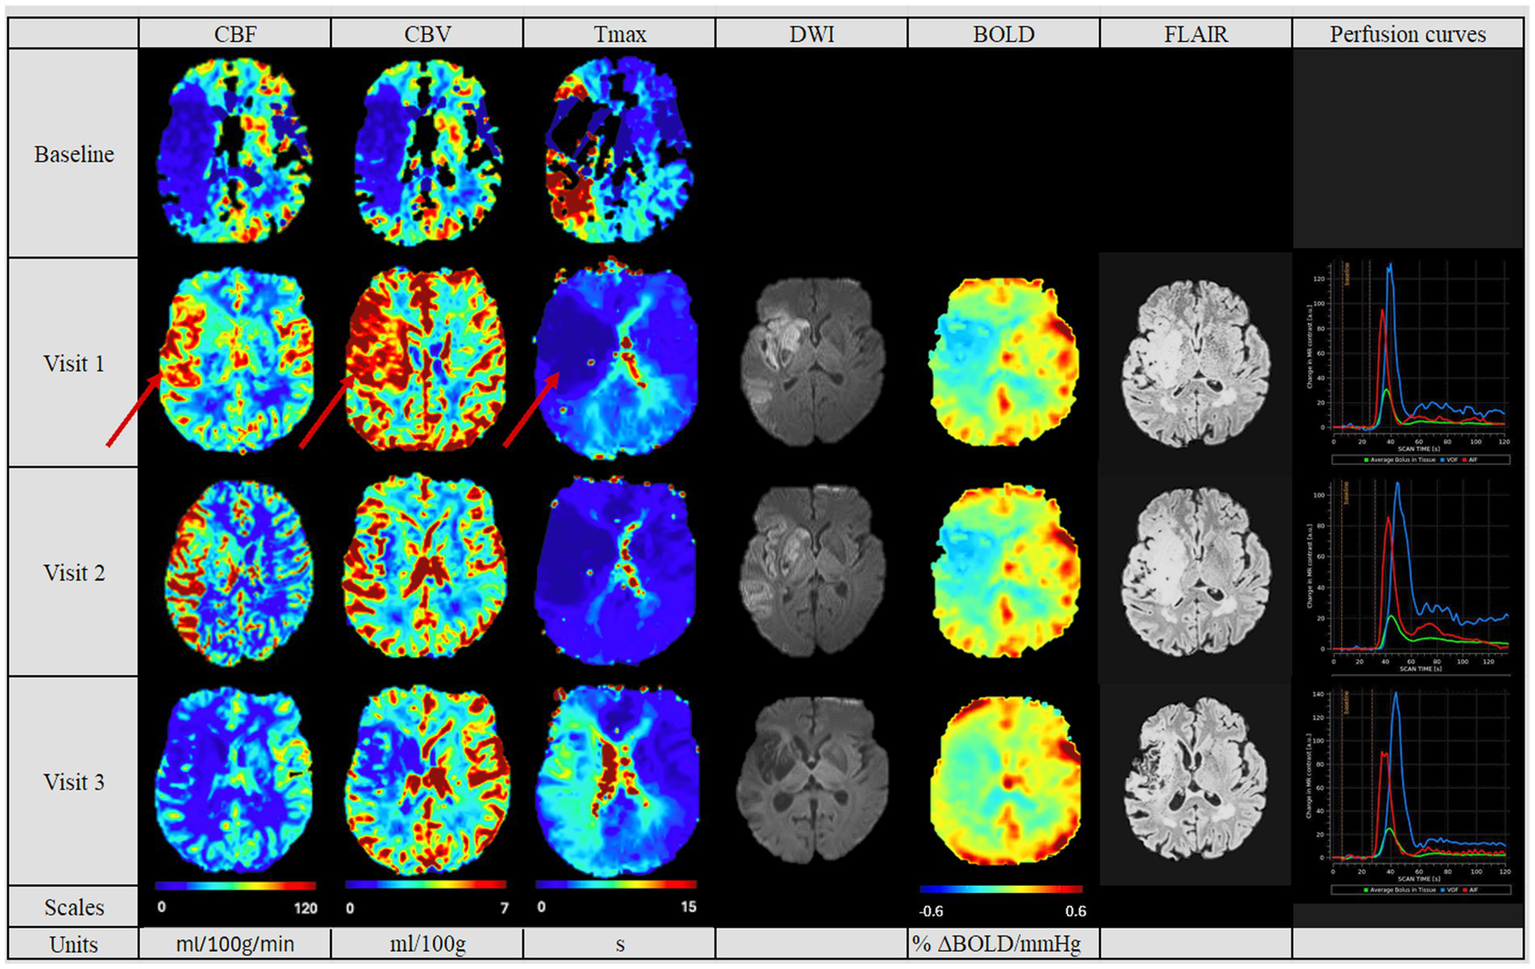

Figure 3

Perfusion pattern “hypoperfusion“: In this perfusion group, patients exhibited after MT a persistently diminished perfusion of the affected side based on CBF, CBV and Tmax values. The difference compared to the contralateral side is pronounced. In addition, perfusion studies including BOLD-CVR (no Visit 3 available), DWI and FLAIR modalities are shown. Finally, perfusion curves show the change in contrast agent over time, where the red line indicates the AIF, the blue line the VOF and the green line the average bolus in tissue. The BOLD-CVR showed persistently slightly diminished values. DWI and FLAIR modalities indicated the persistently compromised brain tissue, reflected in the second largest lesion size of the cohort. The hypoperfused area in Visit 1 on the CBV and CBF maps is indicated by red arrows. Visit 1 was performed <72 hours, Visit 2 7 ± 2 days, and Visit 3 90 ± 14 days after onset. AIF: Arterial Input Fraction, BOLD-CVR: Blood Oxygenation-Level dependent Cerebrovascular Reactivity, CBF: Cerebral Blood Flow, CBV: Cerebral Blood Volume, DWI: Diffusion Weighted Imaging, FLAIR: Fluid Attenuated Inversion Recovery, MT: Mechanical Thrombectomy, Tmax: Time-to-Maximum VOF: Venous Output Function.

In the follow-up PWI studies, the groups with the normalized perfusion after MT (Figure 2) retained their normalized perfusion pattern over all follow-ups. Similarly, for the hypoperfusion group (Figure 3), we observed a persistent circumscribed hypoperfused area without detectable changes in any follow-up. There was no case with later reperfusion. In contrast, the hyperperfusion group showed a tendency to develop a hypoperfusion in the initially affected hyperperfused area between visit two and three (7 days (+/− 2 days) and 90 days (+/− 14 days), see Figure 3), with respective decreased CBF, CBV and increased Tmax values.

The final infarct volume was estimated by quantifying lesion volume from the fluid-attenuated inversion recovery (FLAIR) at visit 3. A tendency for the largest infarct volumes were found in the hyperperfusion group, followed by the hypoperfusion group and the normalized group (35,278 cm3 [Q1–Q3 10,989–61,143], 11,276 cm3 [Q1–Q3 10,352–28,460 cm3] and 4,456.6 cm3 [Q1–Q3 1,493–12,660 cm3], respectively, p = 0.353, see Table 2). Also, we saw a tendency for a better collateral status for the “normalized” group, while this was the poorest for the hyperperfusion group (good status in normalized group for 6 (75%) patients, vs. 2 (33%) in hyperperfusion group, p = 0.657).

In Table 3 we summarized the results of the advanced perfusion studies with BOLD-CVR and NOVA. Within the BOLD-CVR analysis, we observed the highest values in the normalized group for the affected medial cerebral artery (MCA) region, while lower and even negative values were observed at visit one for the hyperperfusion group (0.12 [Q1–Q3 0.09–0.19] vs. − 0.01 [Q1–Q3–0.02-0.07], p = 0.049).